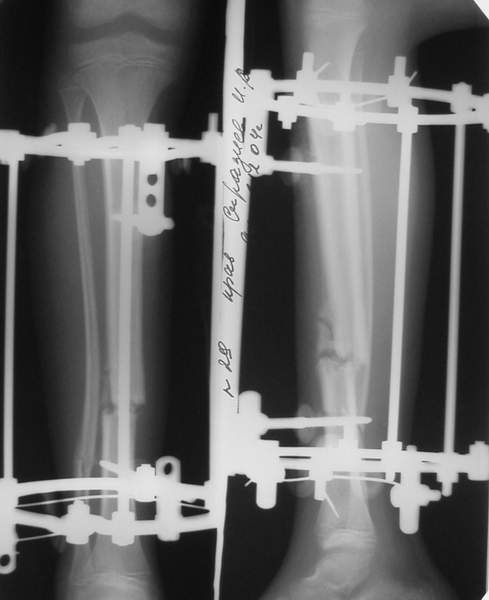

Под рукой прилагаемый пример. Как видите, "стриптиз-аппарат" (шутка проф. З.К.Башурова): 3 кольца-2 кольца-2 полукольца. В случае, который представил Евгений, характер повреждения позволил бы сразу использовать аппарат на основе 2 колец; в крайнем случае прокс. опора м.б. демонтирована сразу после репозиции.

3a

3b

3c

В аттачте № 3 - один из примеров полукольцевого аппарат...

Это уже я баловался.

Итог? Работы больше (по времени и

интраоп "подгонке"), срастается также, а особого преимущества по сравнению с

"чиста" кольцевым (вес, удобство ношения и пр.) - я, по крайней мере,

не нашел.

Теперь не балуюсь.

МТ мы используем, конечно, не только на голени. В прилагаемом примере у парня при поступлении была наружная ротация 40 гр. и "полумертвый" коленный сустав. Можно был бы, конечно, до конца использовать полную компоновку. Но для того он и есть метод выбора.